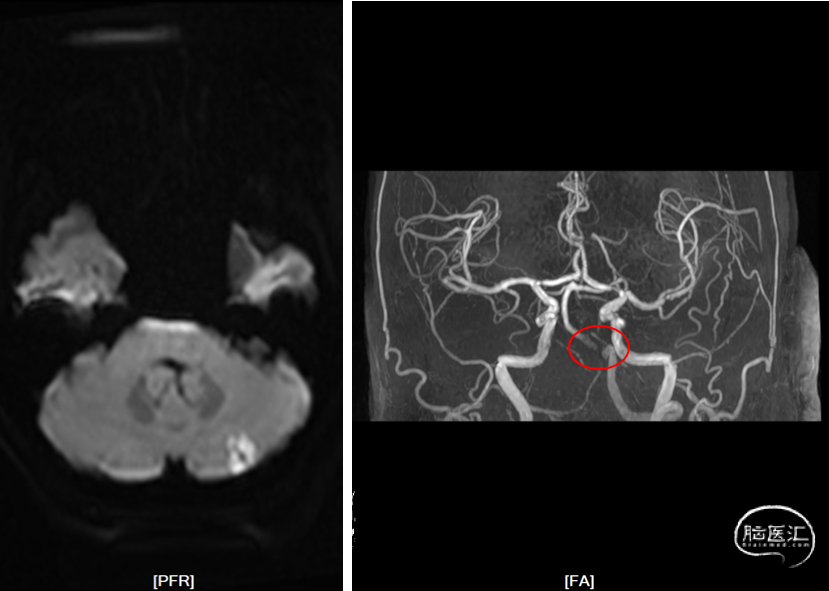

脑血管壁高清MR+灌注(2022-01-14):

DWI

MRA

高清血管壁

头颅灌注

高清血管MR示:双侧椎动脉颅内段及基底动脉近段管壁多发易损斑块形成,管腔重度狭窄,右侧椎动脉局部未见显示;PWI示:小脑及脑干灌注减低。